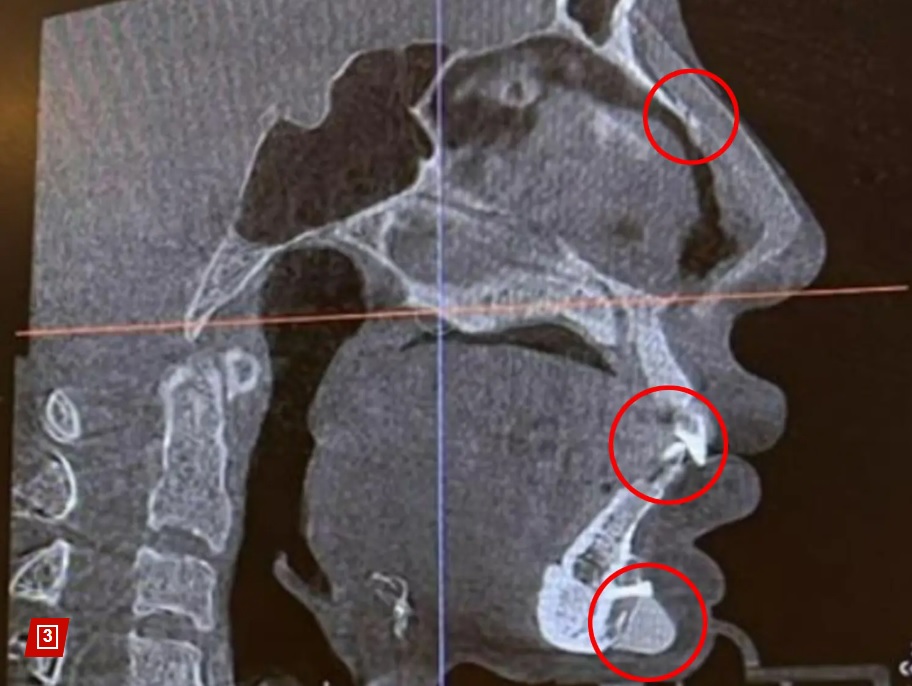

„Fața mea arată ca un puzzle!”, ar fi spus modelul în lacrimi, când a descoperit ce se află în corpul ei.

Controlul cu scanner din aeroprot ar fi semnalat prezența unui șurub chirurgical de 1 centimetru chiar sub buza de jos. Modelul crede că acel șurub a fost în corpul ei de când și-a pus o „proteză de bărbie”, în urmă cu opt ani.

„Am descoperit în mod neașteptat că am și unghii pe nas”, a mai exclamat modelul, șocată de ce a văzut că se află în corpul său.

Fang Qiyuan, în vârstă de 36 de ani, se autointitulează „fanatică a chirurgiei plastice”. Femeia are peste 19 operații plastice, între care două operații la frunte, cinci la pleoape, cinci la nas, două în bărbie și liposucție pentru repararea feței de cinci ori.